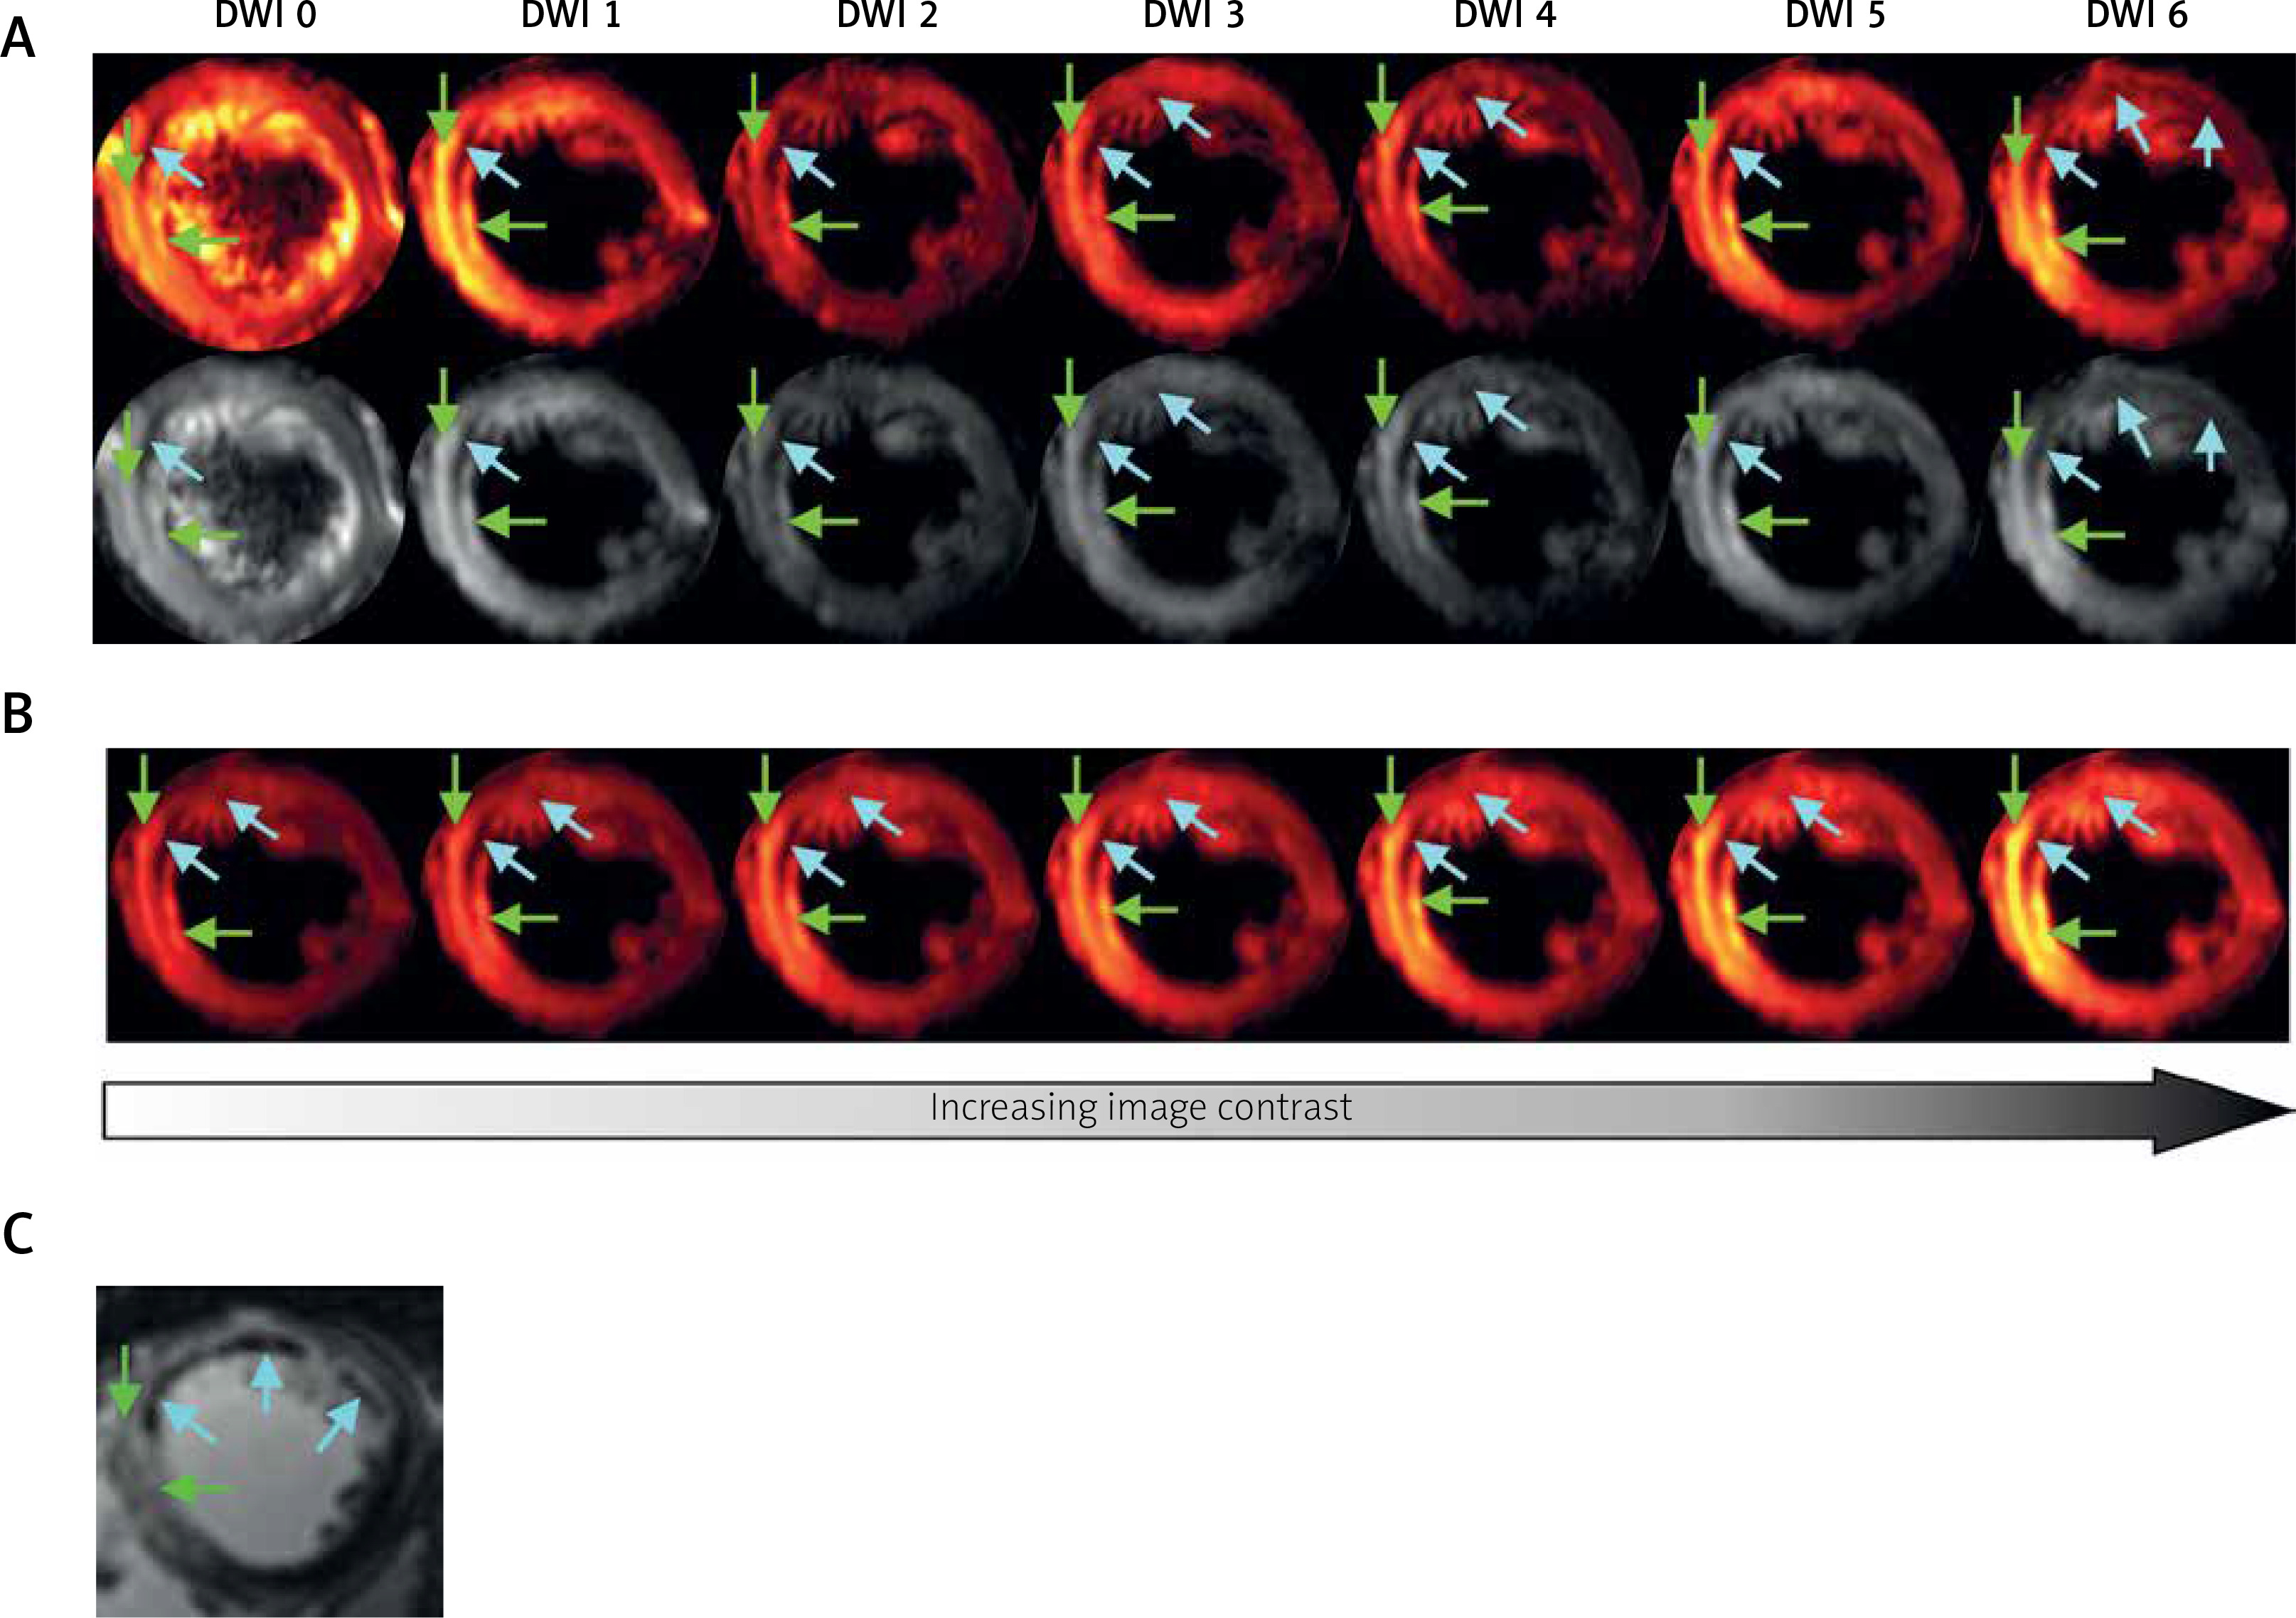

Diffusion has been proposed as a natural biomarker for many diseases, mainly neurodegenerative [24, 25], but also musculoskeletal [26, 27] or cardiovascular [28–30]. Despite their potential, DWI and DTI indices are not used routinely in clinical practice as biomarkers of cardiovascular diseases, since they require sophisticated experimental methods as presented above. However, it was recently shown that based on standard SE-EPI, DTI is feasible for patients with acute myocardial infarction (AMI) (Table I), when sequence parameters are carefully chosen on the basis of a pilot DTI [29]. Figure 3 presents images from DTI examination of a patient with AMI, shortly after pPCI (5 days), applying the same sequence design. The results showed a very good agreement with late gadolinium enhancement images, including infarction damage zones as well as microvascular obstruction. This proves that DTI has potential to be commonly used in clinical practice for AMI patients as an alternative to gadolinium contrast agent (Table I). Hopefully, this and similar applications will be used routinely and pave the way for more advanced methods to enable accurate quantitative DTI and diffusion to become a natural biomarker of cardiovascular diseases. Although progress in cardiac DTI is clearly visible, more solutions are sought to bridge the gap between the scientific development and clinical practice.

Figure 3

Images from patient with AMI (5 days after pPCI) obtained by using SE-EPI DTI sequence with details given previously [29]. A, B – and T1-weighted imaging with late gadolinium enhancement. A – Raw DWI images for b = 0 s mm–2 (DWI 0) and for six non-collinear diffusion gradient directions (DWI 1-6) required for diffusion tensor calculation: hot scale (upper row) and grey scale (bottom row); B – method for visualization of damage zones with different severity by using increasing image contrast; C – T1-weighted image with late gadolinium enhancement. Green arrows indicate infarction area – hyperintense spots in comparison to remote tissues, while blue arrows indicate microvascular obstruction – signal loss